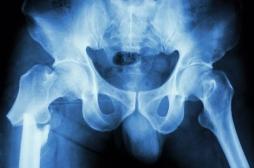

J'AI MAL

J ai Mal Bras et mains Bras et mains Tête et cou Torse et haut du dos Jambes et pied